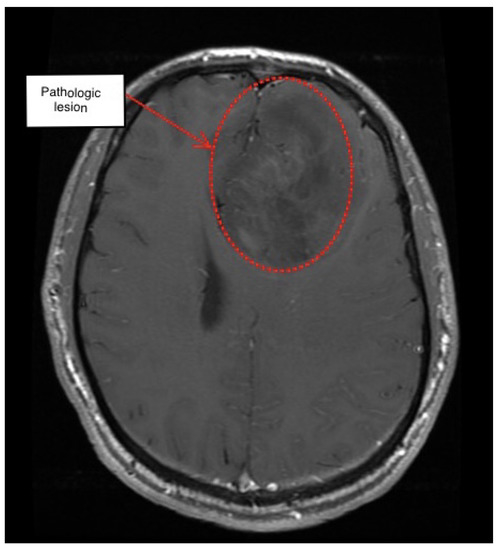

3.1. First Scenario